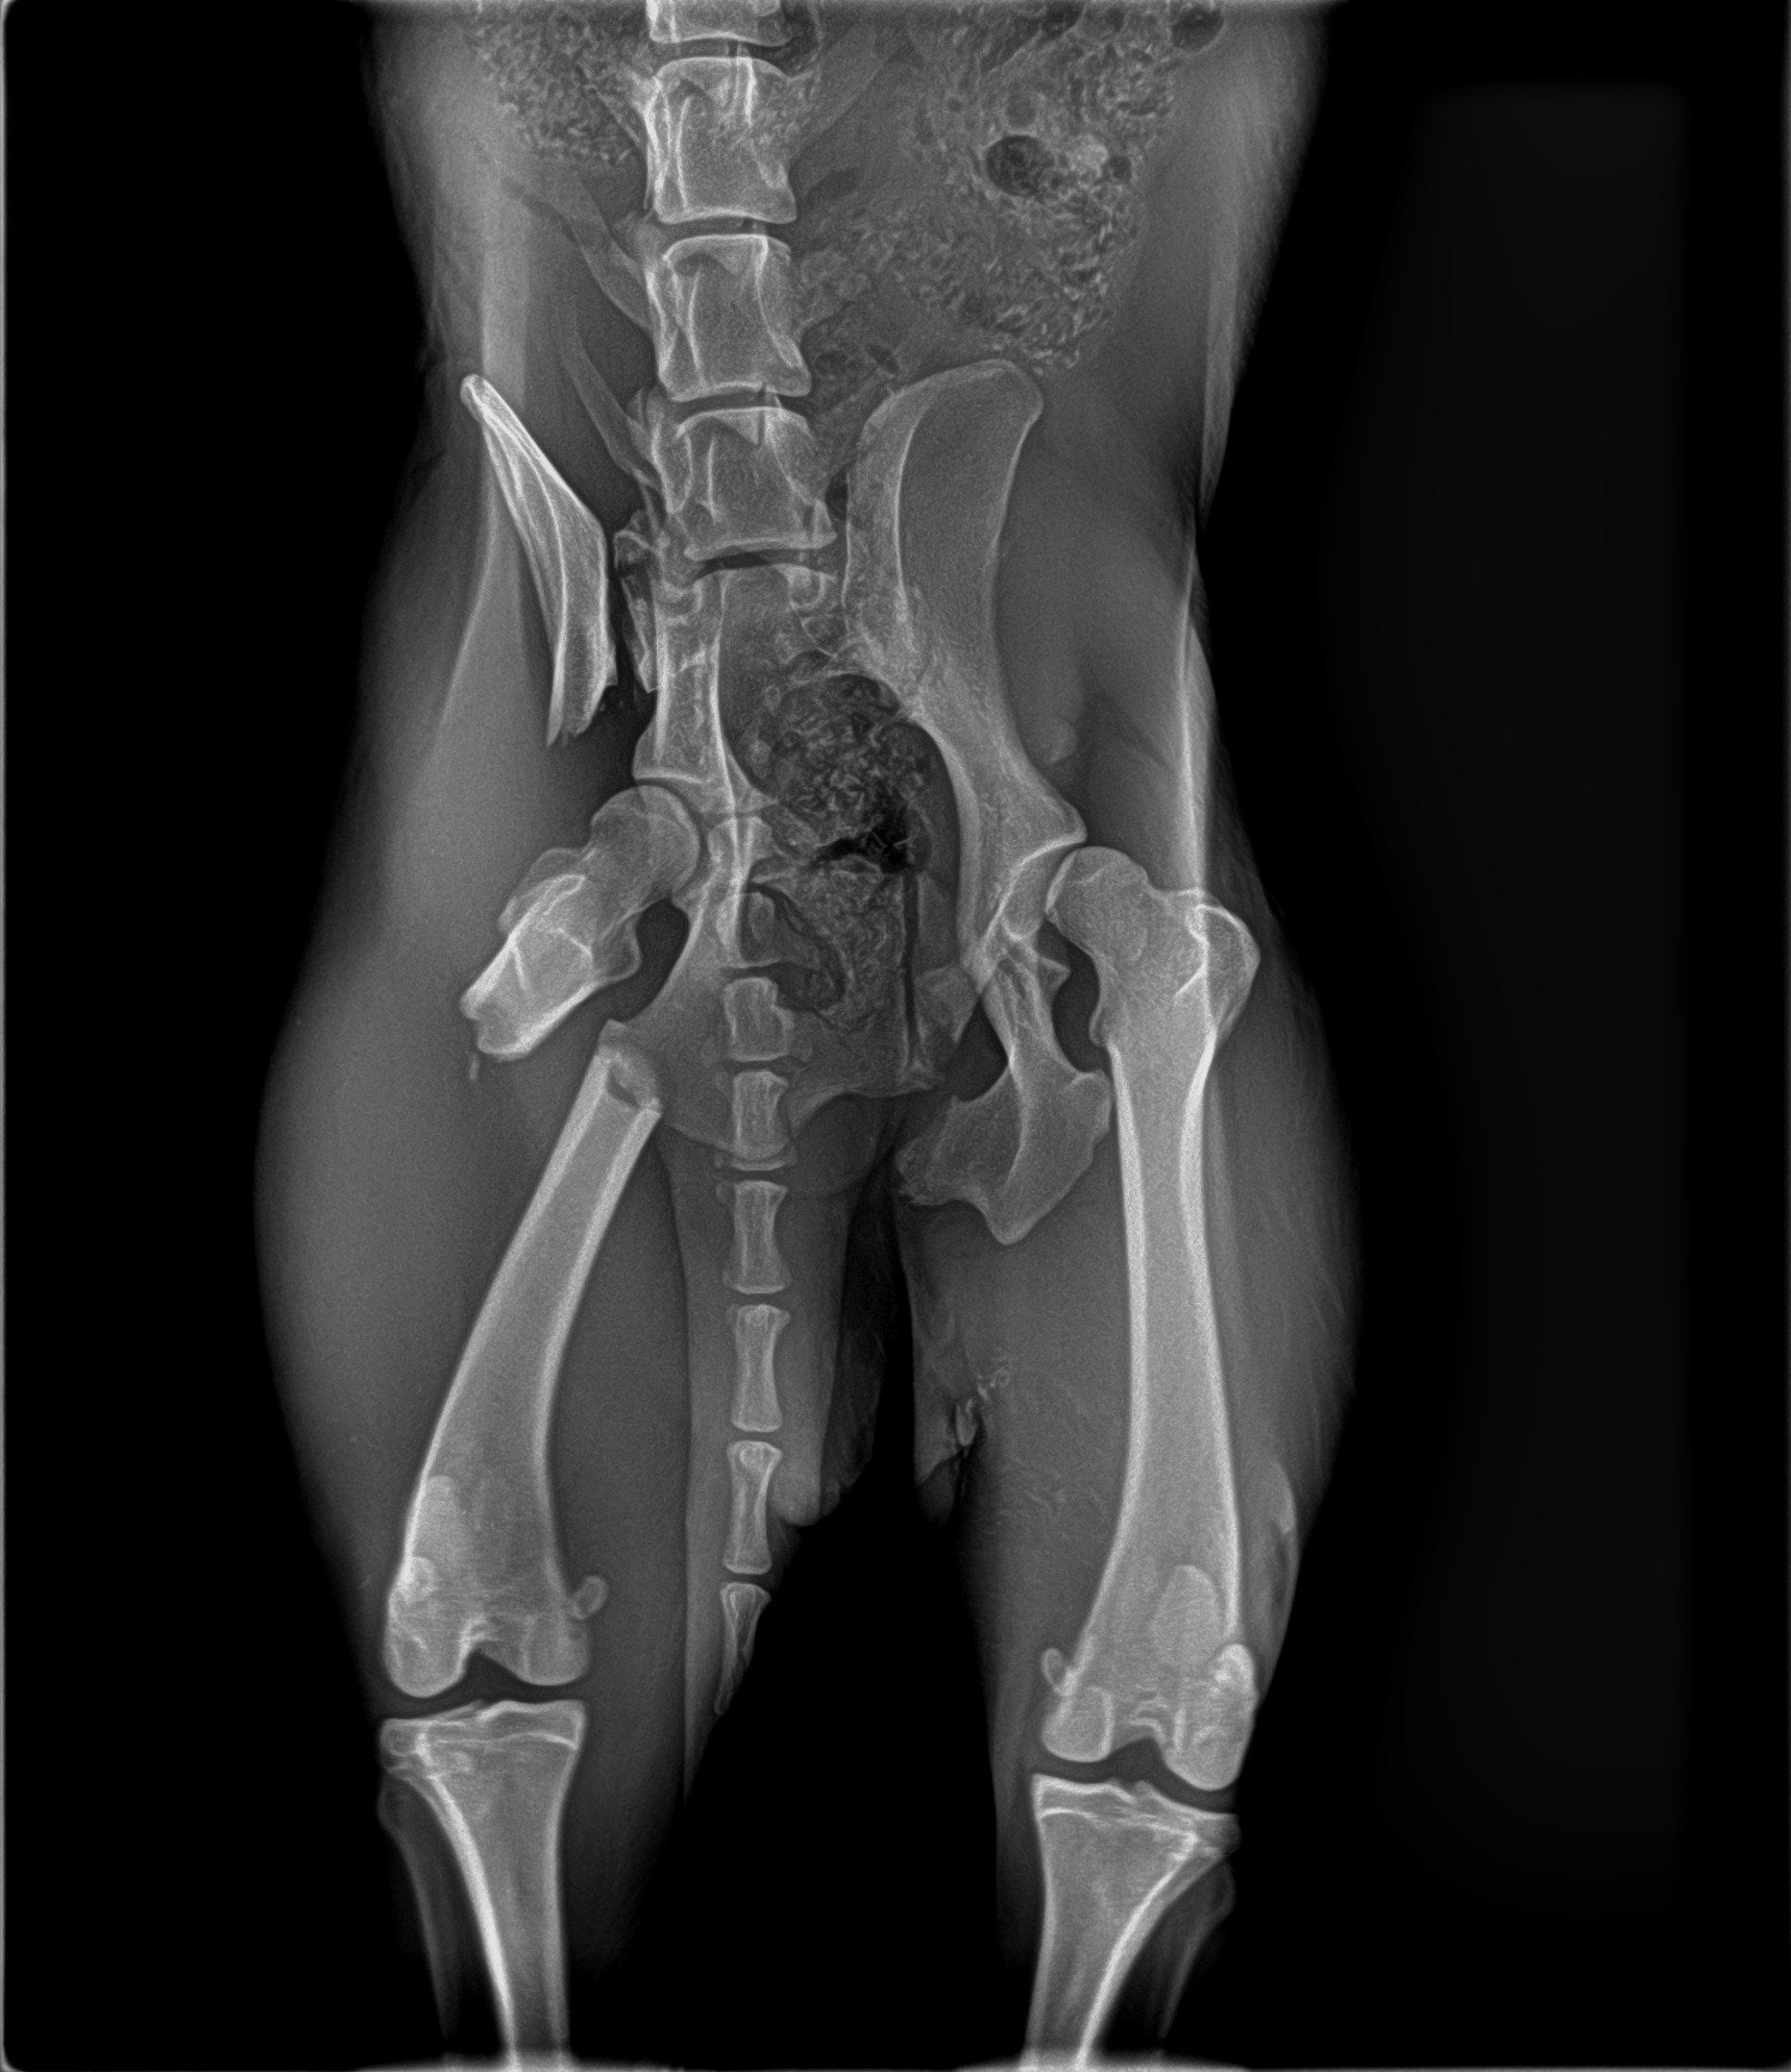

Sushy apareció atropellada en la carretera, de alli la llevaron a la perrera, donde querian sacrificarla, por suerte unas personas la sacaron y nos pidieron ayuda para ella, despues de traerla desde valencia ingreso en un hospital veterinario donde la operaron 3 veces, se paso varias semanas ingresada y cuando por fin salio a una casa de acogida se dio cuenta de que engordo en 3 dias y se le inflamaron las mamas.